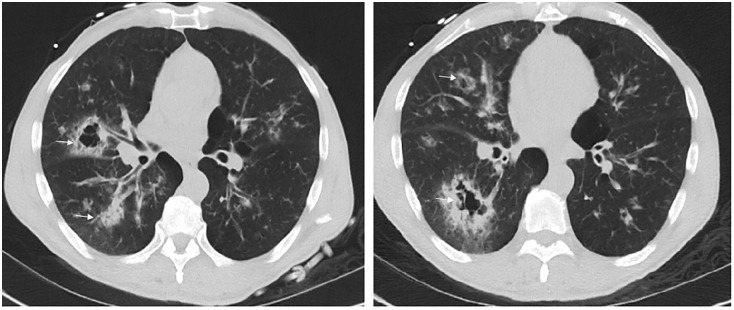

高血糖危机,包括糖尿病酮症酸中毒(DKA)和高血糖高渗状态(HHS),显著影响临床结果并造成沉重的经济负担。在不断增加的娱乐性药物滥用中,可卡因已成为最常被滥用的物质。然而,人们对可卡因使用与高血糖危机之间的关系了解有限。我们回顾性报告了4例可卡因滥用与DKA/HHS之间的关系。在病例1中,1型糖尿病(T1DM)患者表现为精神状态改变和DKA和HHS合并,其中可卡因使用导致错过胰岛素剂量,导致危机。病例2为同一例患者,后来因空洞性肺炎和败血症发展为DKA,需要机械通气、血管加压药和肾脏替代治疗。可卡因吸入导致肺部损伤,引发DKA。病例3涉及一名2型糖尿病(T2DM)患者,他静脉滥用可卡因,导致DKA-HHS和坏死性筋膜炎,需要紧急手术。病例4是一名肥胖、胰岛素抵抗和2型糖尿病患者,服用口服药物,可卡因可能加剧胰岛素抵抗并引发DKA。在所有4例病例中,治疗重点是积极补液、胰岛素输注、电解质纠正和解决潜在原因。高血糖危机在12至24小时内得到解决。然而,控制可卡因相关并发症证明是困难的,导致高发病率和死亡率,包括因呼吸道问题导致的精神状态改变、肾衰竭、横纹肌溶解和可能导致感染性休克或死亡的感染。在病例4中,可卡因使用显著加重了胰岛素抵抗和2型糖尿病,导致DKA。综上所述,可卡因滥用有多重影响,可以通过导致胰岛素剂量不足、脱水、感染和胰岛素抵抗的慢性恶化而引发高血糖危机。可卡因滥用可通过多种机制触发和/或加重高血糖危象,如对心肺和肾脏系统的损害、社会心理变化、免疫力减弱和感染,以及激素和代谢的改变(图3)。我们建议将药物滥用问题纳入常规的患者病史评估和进行毒理学筛查,特别是对经常入院的DKA/HHS患者。此外,我们分享我们在管理这一特定患者群体方面的专业知识。

Hyperglycemic crises, including diabetic ketoacidosis (DKA) and hyperglycemic hyperosmolar state (HHS), significantly affect clinical outcomes and impose a heavy economic burden. Among the steadily increased recreational drug abuse, cocaine has become the most frequently misused substance. However, there is limited understanding of the relationship between cocaine use and hyperglycemic crises. We report 4 cases retrospectively to examine the relationship between cocaine abuse and DKA/HHS. In Case 1, a patient with Type 1 diabetes mellitus (T1DM) presented with altered mental status and a combination of DKA and HHS, where cocaine use led to missed insulin doses, resulting in the crisis. Case 2 involved the same patient who later developed DKA due to cavitary pneumonia and sepsis, requiring mechanical ventilation, vasopressors, and renal replacement therapy. Cocaine inhalation caused pulmonary damage that triggered DKA. Case 3 involved a patient with Type 2 diabetes mellitus (T2DM) who abused cocaine intravenously, leading to DKA-HHS and necrotizing fasciitis that required emergency surgery. Case 4 was a patient with obesity, insulin resistance, and T2DM on oral medications, where cocaine likely exacerbated insulin resistance and triggered DKA. In all 4 cases, treatment focused on aggressive rehydration, insulin infusion, electrolyte correction, and addressing underlying causes. The hyperglycemic crises resolved within 12 to 24 hours. However, managing cocaine-related complications proved difficult, leading to high morbidity and mortality rates, including altered mental status with airway issues, kidney failure, rhabdomyolysis, and infections that could result in septic shock or death. In Case 4, cocaine use significantly worsened insulin resistance and T2DM, contributing to DKA. In conclusion, cocaine abuse has multiple effects and can act as an unusual trigger for hyperglycemic crises by causing missed insulin doses, dehydration, infections, and chronic worsening of insulin resistance. Cocaine abuse can trigger and/or worsen hyperglycemic crises through various mechanisms, such as damage to the cardiopulmonary and renal systems, psychosocial changes, weakened immunity and infections, and alterations in hormones and metabolism (Figure 3). We suggest incorporating questions about substance abuse into routine patient history assessment and performing toxicology screenings, particularly for individuals who have frequent admissions for DKA/HHS. Additionally, we share our expertise in managing this specific group of patients.